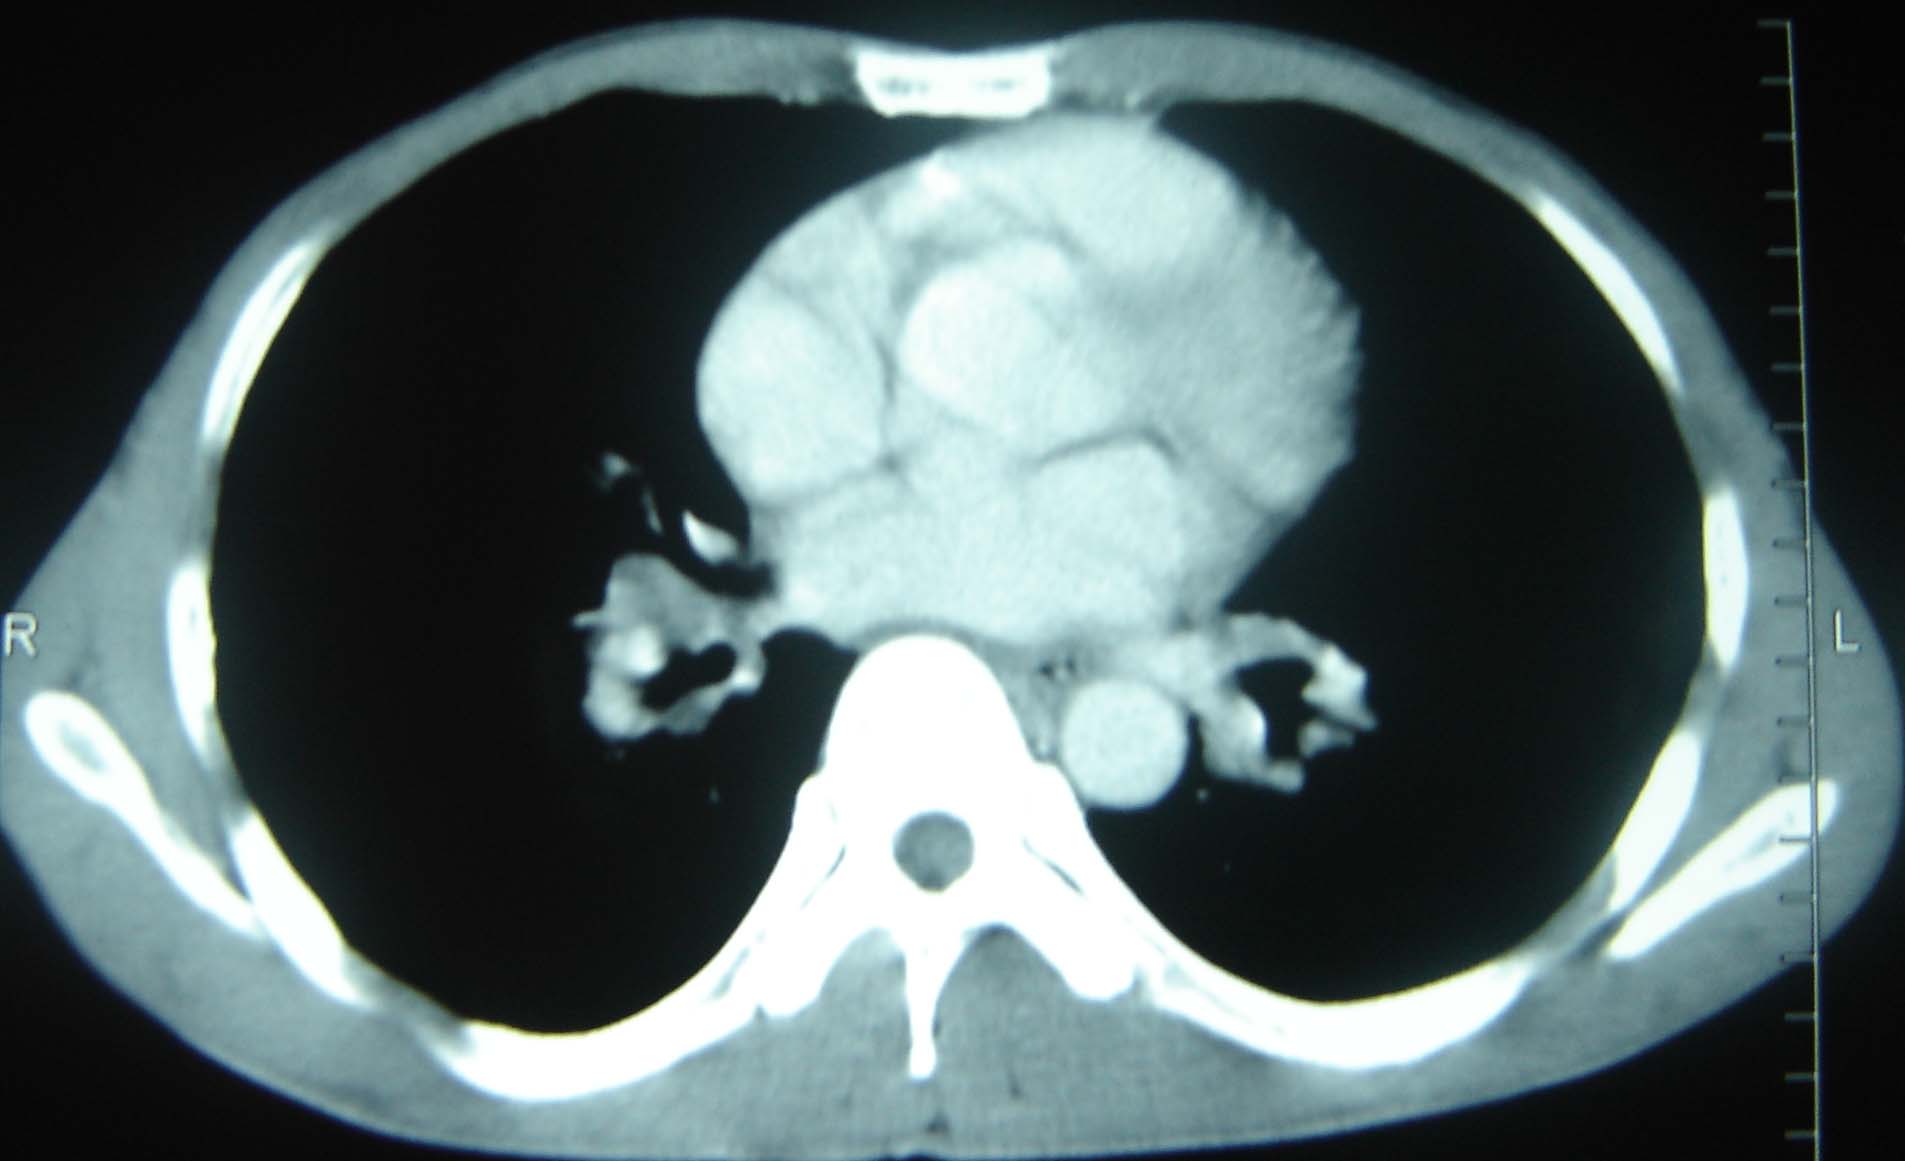

标题: CT25321:两肺多发结节 请会诊 [打印本页]

标题: CT25321:两肺多发结节 请会诊

男 、43岁,咳嗽胸痛,装修工,平时接触粉尘较多,有吸烟史10多年,纤维支气管镜检查未发现异常,胃镜、腹部b超检查亦未发现异常,颈部淋巴结活检未发现肿瘤细胞。

不能排除转移,如果不能找到原发灶,只有短期随访。

结节病?转移瘤?

1)考虑双肺及胸膜多发性转移瘤。2)肺气肿。